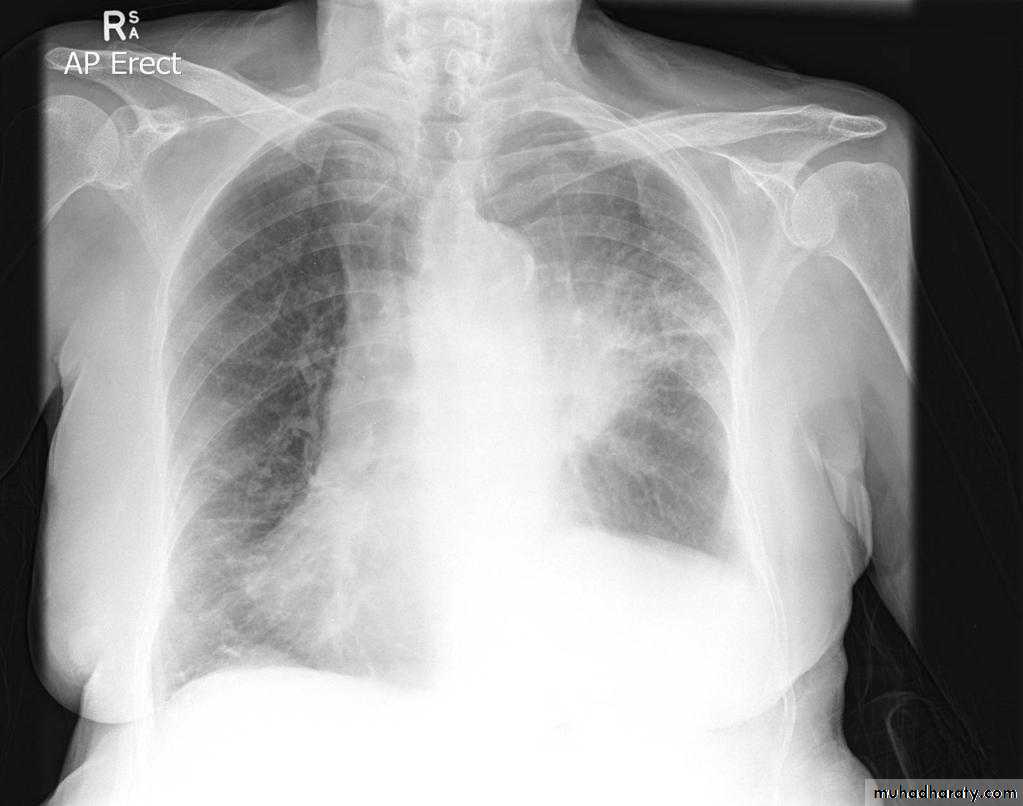

Lobular consolidation ( broncho pneumonia )

Very important to consider that pulmonary edema in normal sized heart have close similar appearance to broncho pneumonia

The important Golden Key differentiation is the cardiac size being enlarged in pulmonary edema .

36.lobuler consolidation (lobular pneumonia )37.discussion